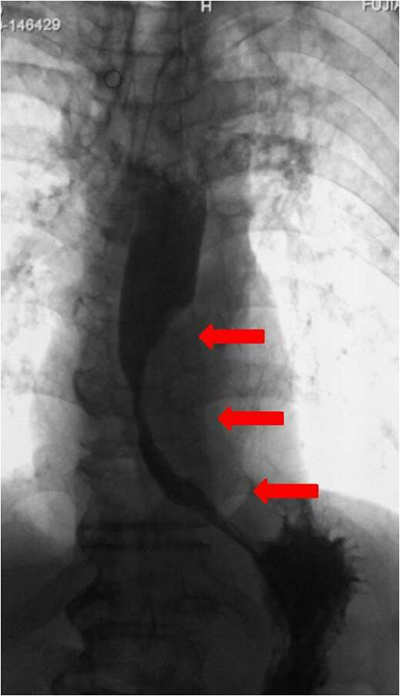

食道中下段癌性狭窄

患者姜先生,85岁,因进行性吞咽困难3月余到院就诊,无法进食,病变位于食道中下段,内镜下证实为食道癌。该病人属于高龄,病情较重、手术耐受力差、手术风险极高,主治医师和家属协商后,决定行食道支架置入术。消化内镜中心副主任医师谢丹与放射科仇亚军主任,经数字胃肠机X线引导准确定位,成功完成食道支架植入术。术后姜先生一般情况良好,吞咽情况得到很好的改善。